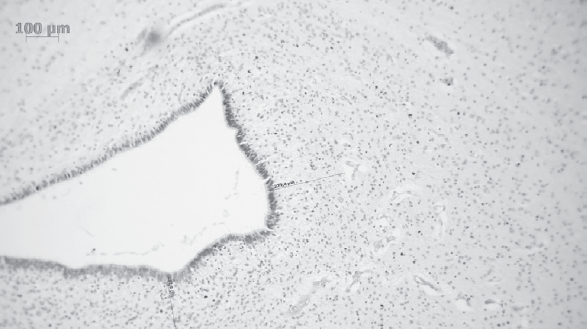

Patterns of neuroplasticity and cerebral maturation in preterm neonate can be assessed by MRI and cranial ultrasound. The score system of brain maturation includes the account of germinal matrix (GM) regression by MRI. The GM regression can be considered as pattern of neuroplasticity. There have been investigated the changes of neuroplasticity pattern or GM regression in preterm neonates with extremely low birth weight (ELBW) without intragerminal/intraventricular hemorrhages (n = 21). It is believe that the main causes of impair of GM are the intragerminal hemorrhages and hypoxia. The methods of study were cranial ultrasound (CU) and MRI. The measurement of GM was carried out by CU in anterior horn of the lateral ventricles of neonates in the study group (25-29 weeks). It was detected the GM regression in preterm neonates with increasing age, and complete GM regression to 30 week. MRI has been performed in 15 neonates from the study group on 27-38 weeks age with using the common pulse sequences – T1 WI, T2 WI and Flair. GM was detected by MRI up to 34 weeks inclusive by using the additional pulse sequence – DWI. By using common pulse sequences the GM was visualized up to 32 weeks age. Furthermore there has been pathological examination of GM in anterior horn of lateral ventricle in dead neonates from the study group (n = 3). We revealed the thickness reduction of GM in the lateral ventricles with increasing age of the dead neonates. Also we identified the delay of the GM reduction in two dead neonates 36-38 weeks age (post conceptual age) what may indicate the disorder of neuroplasticity in those preterm neonates. The performed study showed the capability of CU and MRI in examination of neuroplasticity in preterm neonates.